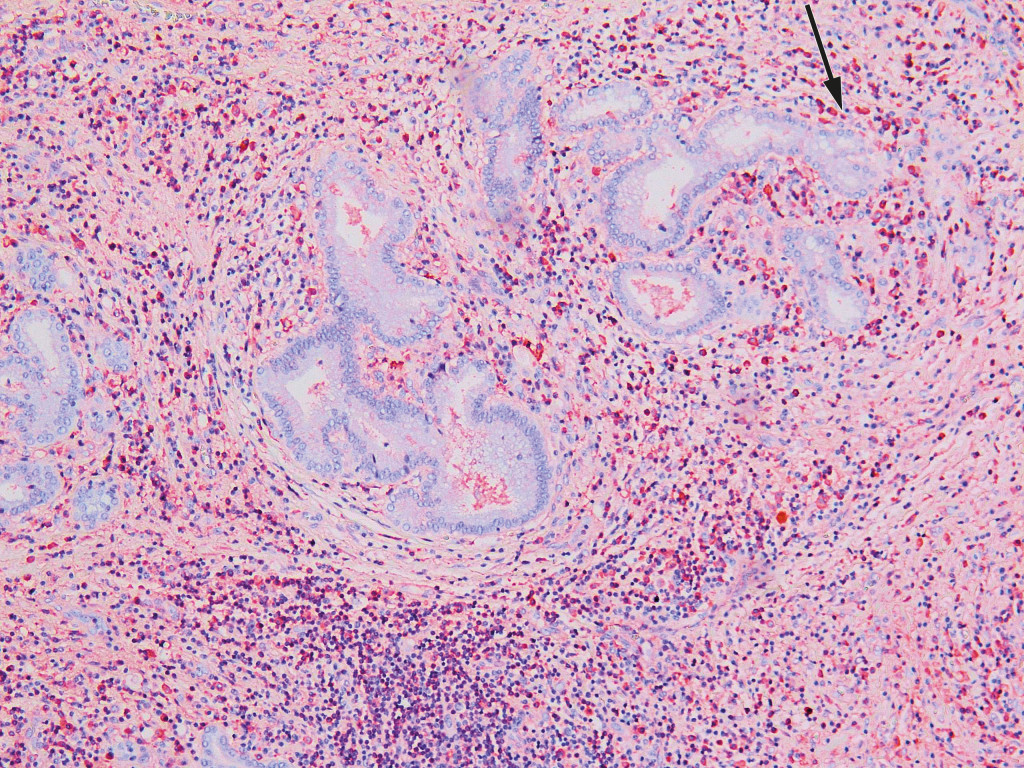

Six days after the transfer, extended right-sided liver resection with hepaticojejunostomy was performed. The patient developed liver failure post-operatively, with subsequent ischaemic necrosis in residual liver tissue. His condition was judged to be very serious with little chance of spontaneous improvement. Examination of the resection specimen was therefore classified as urgent, in case the condition should prove to be benign and hence allow transplantation. A histological sample from the liver hilum showed no signs of malignancy, but lymphoplasmacytic infiltrates and abundant eosinophil granulocytes. Immunohistochemical analysis revealed an excess of IgG4-positive plasma cells and an elevated IgG4/IgG ratio of over 0.4 (Fig. 2). Serum-IgG4 concentrations were measured post-operatively, and found to be elevated at 6.0 g/l (0.03–2.01 g/l). The findings were consistent with IgG4-related disease.

Characteristic tissue biopsy findings obtained by immunohistochemical analysis, with lymphoplasmacytic inflammation, storiform fibrosis and a ratio of IgG4- to IgG-positive plasma cells of over 0.4 are regarded as the gold standard, but the diagnosis must be based on a combination of radiological, pathological and serological findings (6). The most widely used sets of diagnostic criteria are the HISORt criteria (histology, imaging, serology, other organ involvement and response to steroid therapy), which were developed for diagnosing autoimmune pancreatitis and later modified for IgG4-related sclerosing cholangitis (7).

The liver resection specimen revealed that the patient had an IgG4-related inflammatory pseudotumour of the liver hilum, which may explain the ineffective biliary drainage. IgG4-related inflammatory pseudotumour of the liver is rarely reported and is most frequently described in the orbit, kidney and lungs. Tissue biopsy of perihilar strictures is largely avoided because of the fear of tumour dissemination and due to the risk of pancreatitis and cholangitis (3).